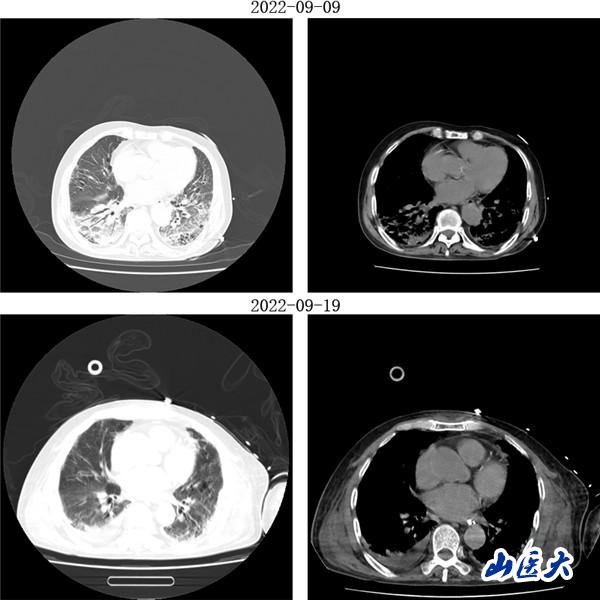

重癥醫學科三病區張文凱主任團隊深入分析了兩位患者的病情。考慮到兩名老年患者均已出現急性呼吸窘迫綜合征,決定采用俯臥位通氣技術為他們治療。在張文凱主任的指導下,侯林義主治醫師帶領張承、孫潔住院醫師對女性患者經俯臥位通氣治療,92小時后復查胸部CT,雙肺明顯好轉,氧合指數由90上升至300mmHg以上,吸氧濃度由100%降至35%,ARDS明顯改善;對男性患者,采用聯合持續性血液濾過(CRRT)治療方案,經俯臥位通氣治療66小時后復查胸部CT,顯示明顯改善,同時氧合指數由102上升至360mmHg左右,吸氧濃度需求下降至40%,全身水腫情況也明顯減退。

(男性患者治療前后胸部CT對比)